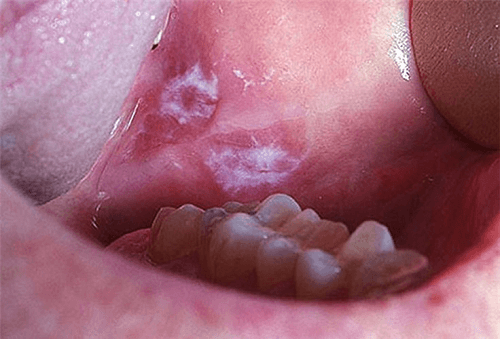

- Thay đổi màu sắc trong khoang miệng: Nổi vệt hoặc đốm nhỏ màu trắng đục hoặc màu đỏ hồng.

- Viêm loét lâu lành trong khoang miệng: Những vết loét không đau, hơi cứng, cộm, vướng.